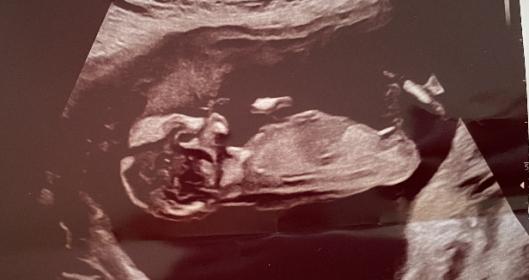

Tricky NUB 13+1 weeks? Long NUB but some stacking?

I had a scan yesterday (13+1 weeks!). During the scan I was convinced I saw long somewhat flat, but also a stacked nub (I saw a shadow in the background), but the tech said it was the stacking was the umbilical cord. The tech said she saw a flat NUB that I is why she was leaning more towards girl.

I posted my scans online and got mostly boy guesses (some girl because of the "flat" NUB) but I was wondering if it's still possible it might be a girl? That the "stacked thing" is something else??? (Already got 3 boys so a girl would be so welcome!)